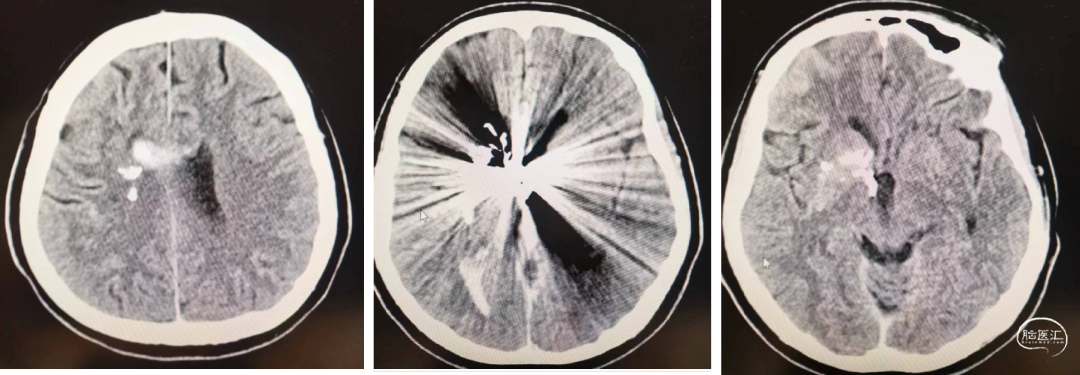

术后复查颅脑CT:少量脑出血,轻微头痛,无偏瘫失语;继续控压90以内,脱水、止血、镇静镇痛。1周后康复。出院